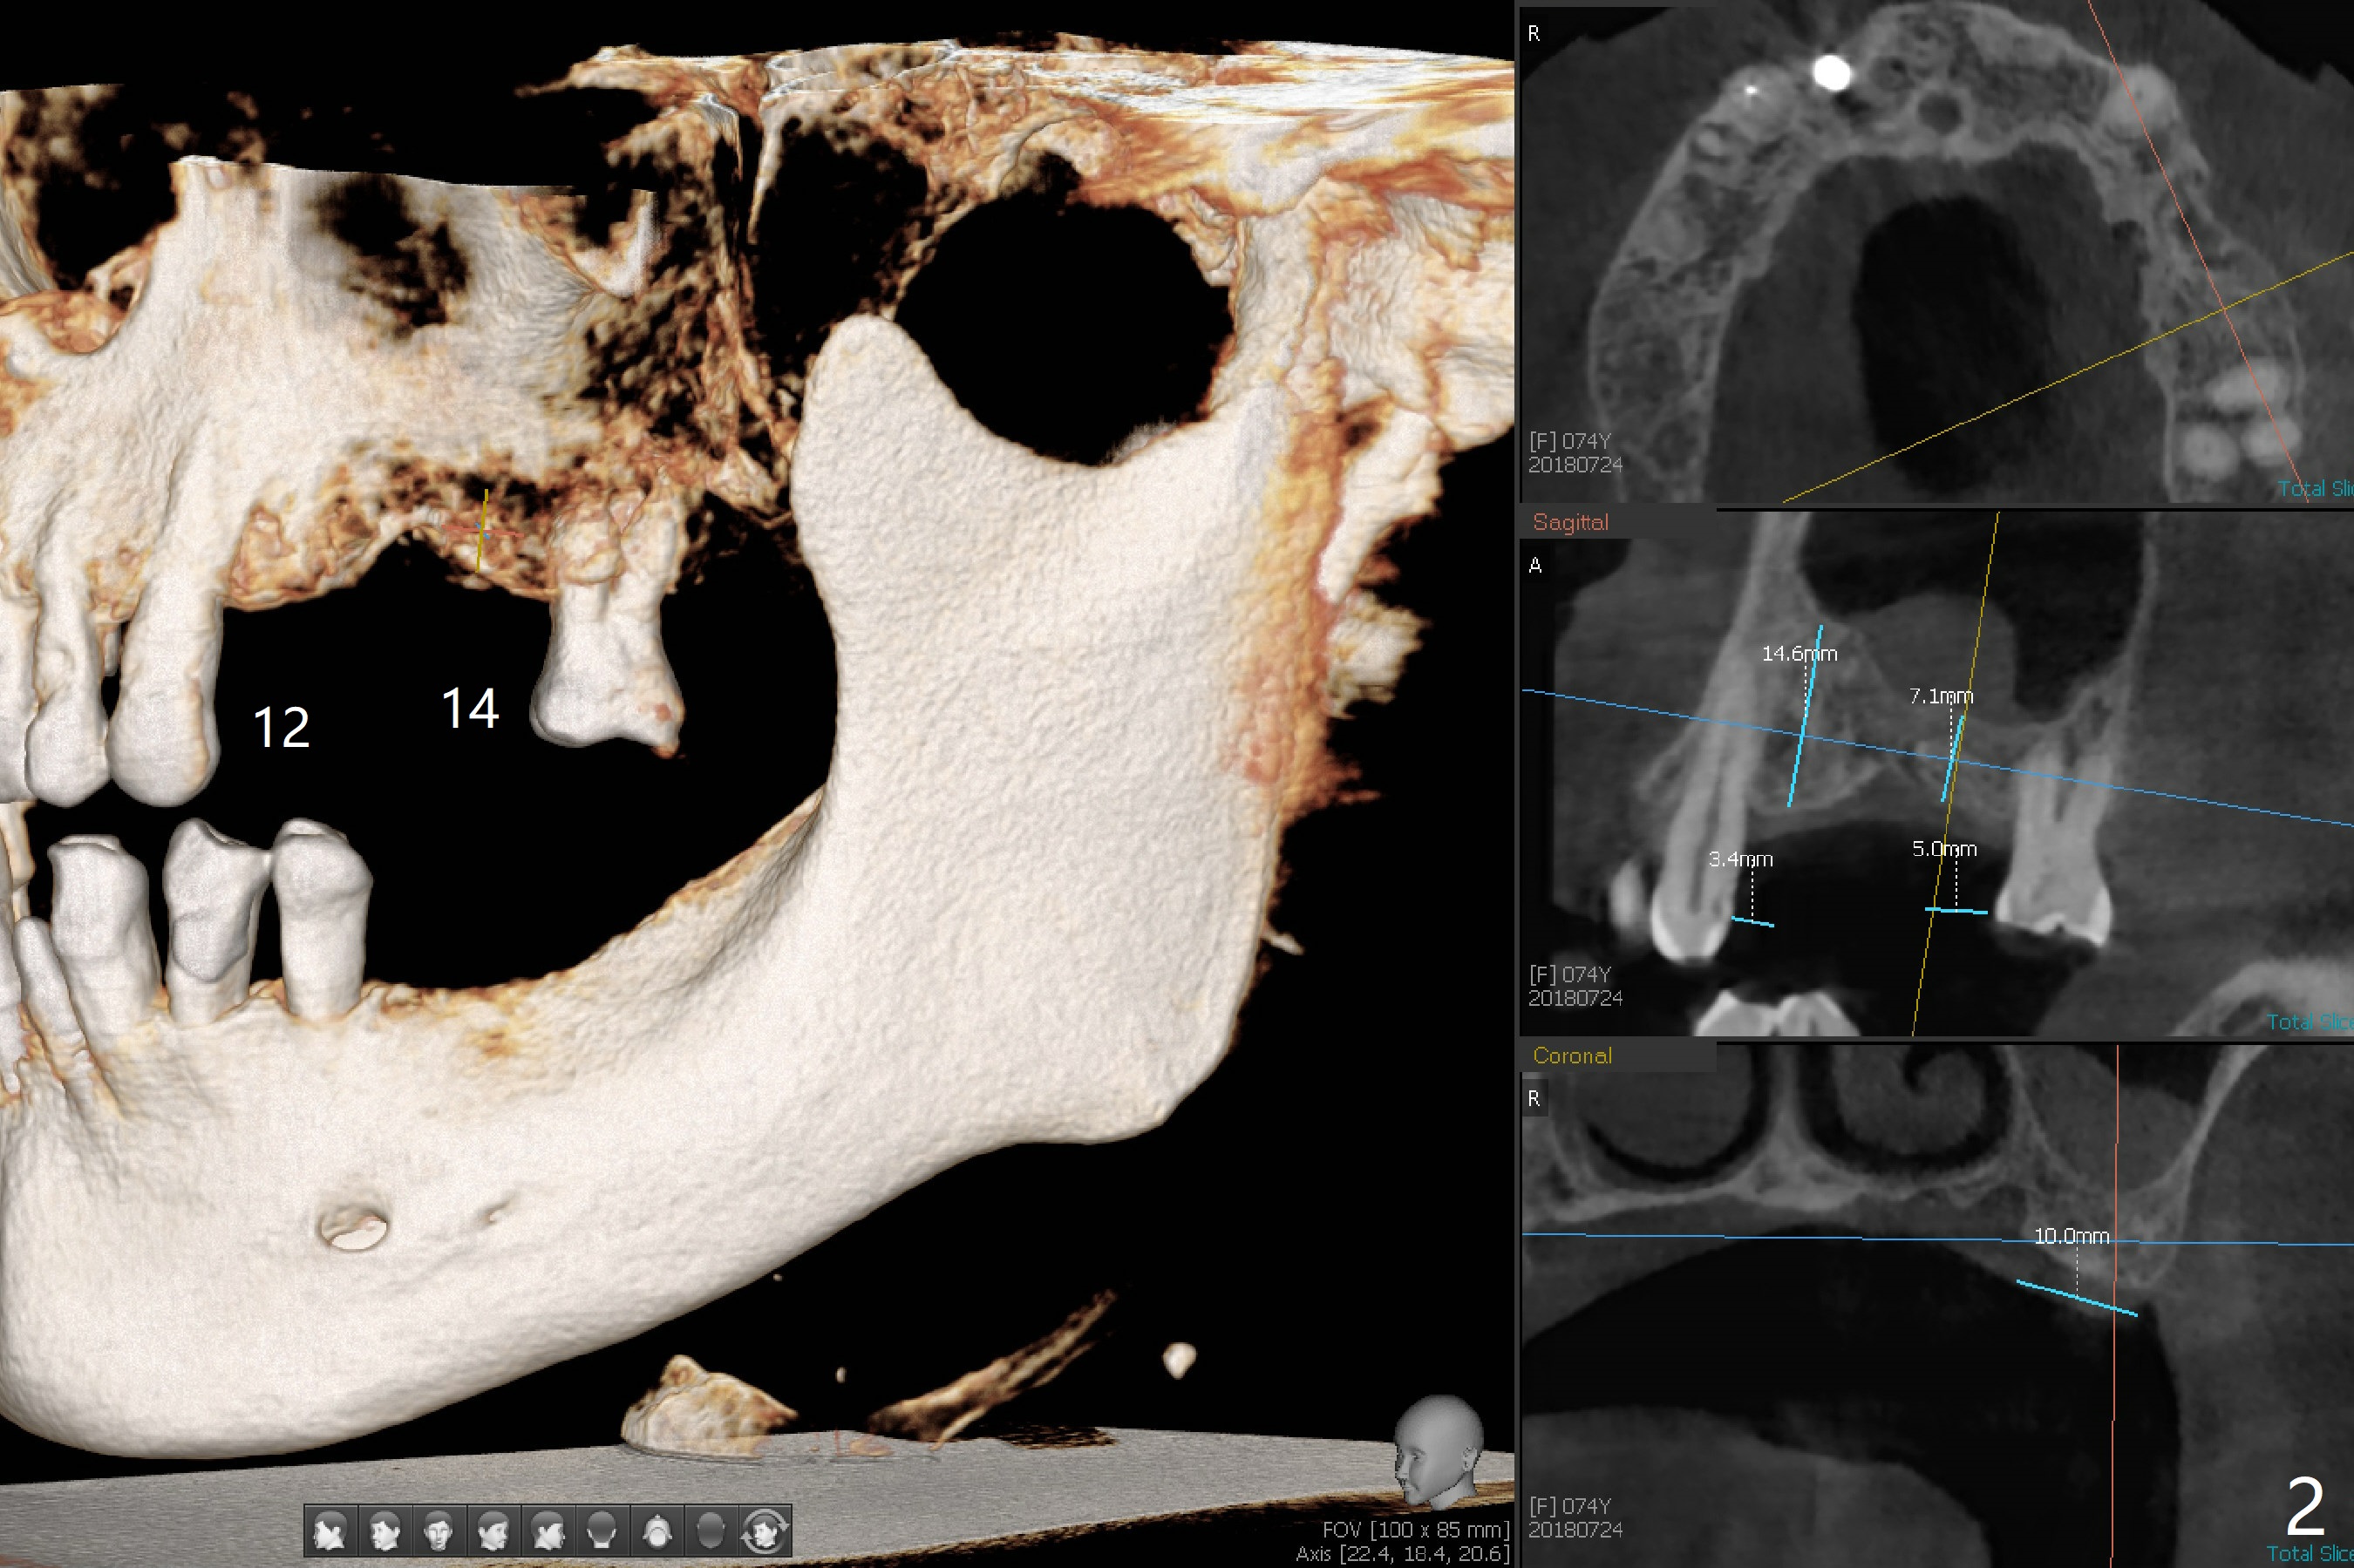

A 74-year-old woman agrees to have implants at #12,14 (for FPD),18 and 19 with guide. Bone height is limited in the molars (Fig.2,3). There is a polyp in the left sinus (Fig.1 *).